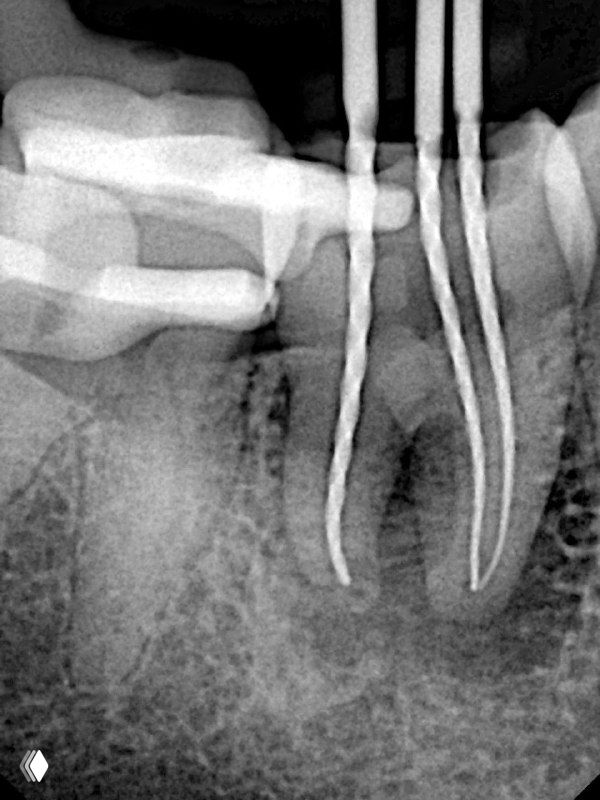

- 4)При препарировании каналов стараюсь придерживаться миниинвазивной концепции: в каналах пошире - до чистых дентинных опилок (25,30.04), в тонких корешках может быть и 20.04. за счёт использования активации ирригационных растворов, можно уменьшить размер препарирования.

- 5) Активирую раствор ультразвуковыми и звуковыми насадками. Они вполне доходят в 20.04 на минус 3 мм от рабочец длины.